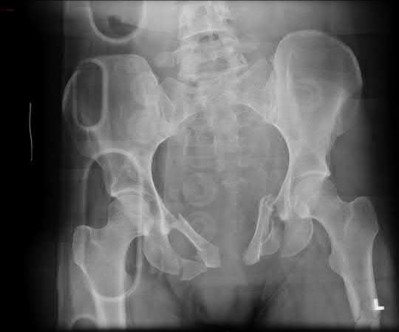

A 23-year-old female is an unrestrained driver in a motor vehicle collision, sustaining the injury shown in Figure A. She subsequently undergoes reduction and percutaneous bilateral iliosacral screw placement. Which of the following is the most likely neurologic complication associated with percutaneous iliosacral screw insertion?

Figure A shows an unstable bilateral pelvic ring injury. Percutaneous posterior iliosacral screw fixation places the L5 nerve root at risk as it courses across the sacral ala. Injury to the L5 nerve root would typically result in weakness in great toe extension and sensory changes on the dorsum of the foot. It is important to notice that L5 often partially innervates tibialis anterior along with L4, so weakness to ankle dorsiflexion may be present as well. Illustration A shows the post-operative films with bilateral iliosacral screws.

Routt et al examined the sacral slope and sacral alar anatomy in cadavers and a series of consecutive patients. They determined that the pelvic outlet and lateral sacral plain films provide the best plain radiographic views of the sacral ala. They recommended routine usage of these views intraoperatively to guide screw placement.

In another study, Routt et al reported on the early complications of percutaneous placement of iliosacral screws for treatment of posterior pelvic ring disruptions. While technically challenging, this technique leads to less blood loss and lower rates of infection compared to traditional open techniques.

Illustration B displays the root diagrams for sensation, reflex, and motor of the L4-S1 nerves.